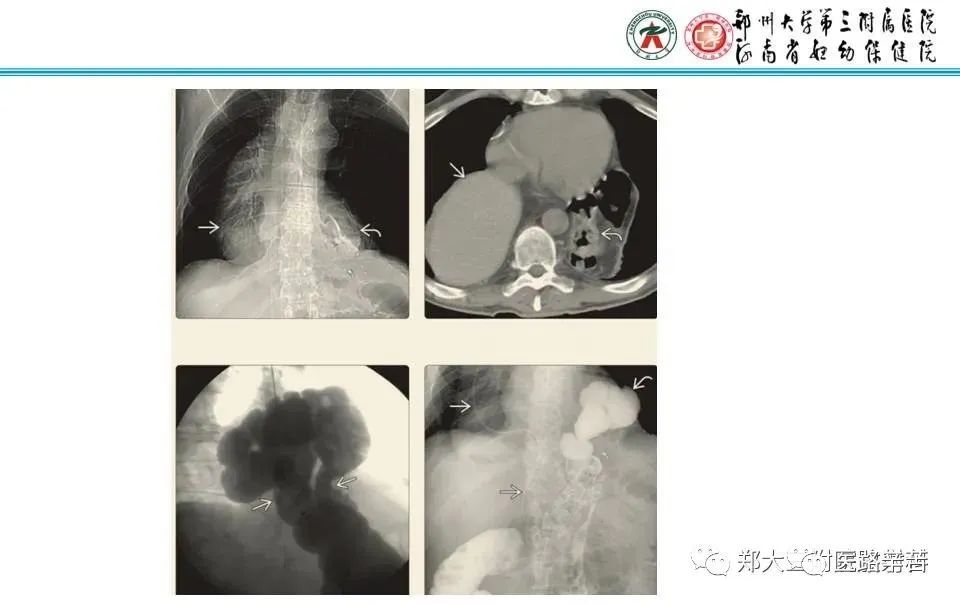

三、Bochdalek疝(胸腹膜疝)

较罕见,老年人居多,多位于右侧,疝容物多为脂肪或网膜,也可以是实性或空腔脏器。

五、创伤性膈疝

外伤时,导致膈肌破裂口较大时,腹内脏器可嵌入胸腔,形成创伤性膈疝。